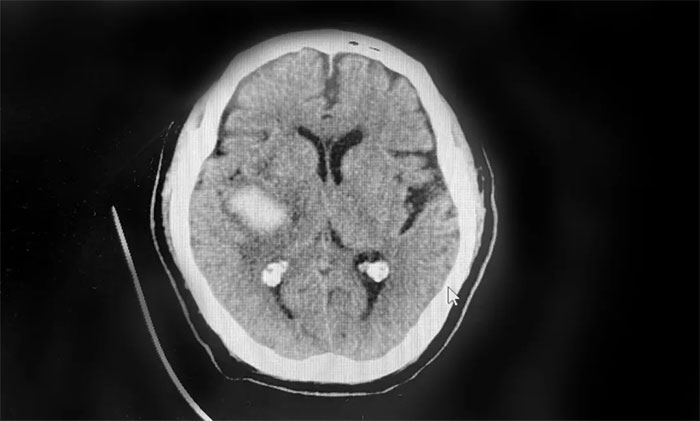

患者徐老伯(化名)今年73歲。今年2月,其在打乒乓時,突感頭暈伴左側(cè)肢體活動不利,送醫(yī)至就近醫(yī)院。經(jīng)查,患者右側(cè)基底節(jié)出血、蛛網(wǎng)膜下腔出血,給予脫水降顱壓等對癥支持治療。

▲ 患者右側(cè)基底節(jié)出血、蛛網(wǎng)膜下腔出血